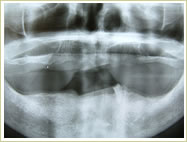

79歳 男性 インプラント埋入数:12本 画像拡大

治療前